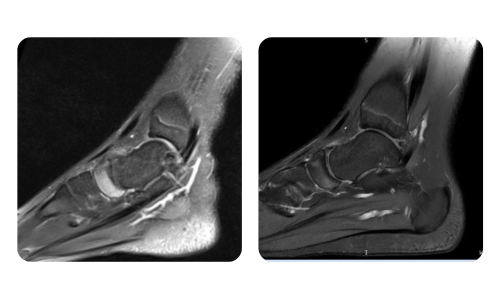

Der Fortschritt unserer Patienten, gemessen vor und nach der hyperbaren Therapie, spiegelt die Effizienz und die positive Wirkung der Behandlung wider. Entdecken Sie dokumentierte Ergebnisse der hyperbaren Therapie in der Klinik Hyperbarium Oradea, basierend auf klinischen Bewertungen und objektiven Daten, die signifikante Verbesserungen bei verschiedenen Erkrankungen belegen.